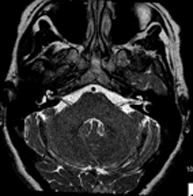

- Brain MRI (cranial)

This non-invasive diagnostic procedure uses an electromagnetic field and radio waves (from a transmitter and receiver) to acquire high-definition anatomical images of the brain. It is a radiation-free procedure. Indicated for: vascular problems, memory loss, epilepsy, headache, malformations, suspected tumour, meningitis.